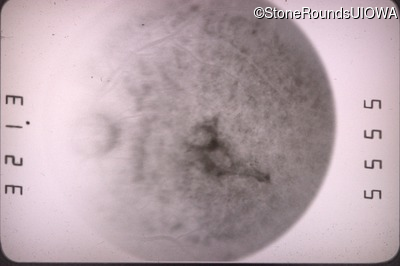

Fluorescein Angiography - Right - 20/100 -1

Exemplar